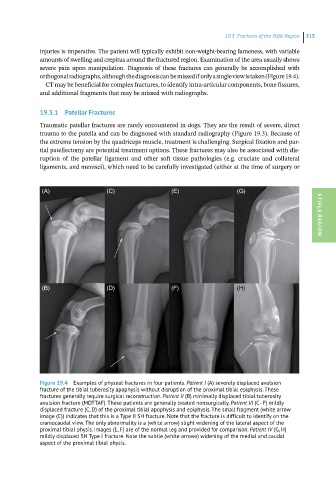

Figure 19.4 Examples of physeal fractures in four patients. Patient I (A) severely displaced avulsion

fracture of the tibial tuberosity apophysis without disruption of the proximal tibial epiphysis. These

fractures generally require surgical reconstruction. Patient II (B) minimally displaced tibial tuberosity

avulsion fracture (MDTTAF). These patients are generally treated nonsurgically. Patient III (C–F) mildly

displaced fracture (C, D) of the proximal tibial apophysis and epiphysis. The small fragment (white arrow

image (C)) indicates that this is a Type II SH fracture. Note that the fracture is difficult to identify on the

craniocaudal view. The only abnormality is a (white arrow) slight widening of the lateral aspect of the

proximal tibial physis. Images (E, F) are of the normal leg and provided for comparison. Patient IV (G, H)

mildly displaced SH Type I fracture. Note the subtle (white arrows) widening of the medial and caudal

aspect of the proximal tibial physis.